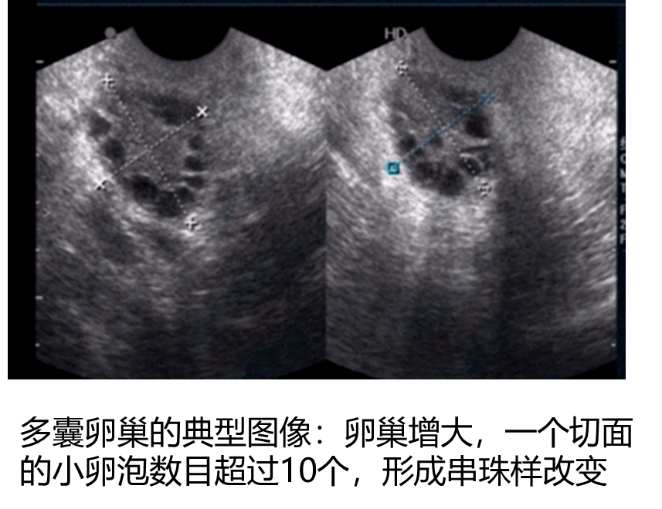

多囊卵巢综合征(PCOS)是临床常见的妇科内分泌代谢疾病之一。多见于育龄期女性。主要表现为月经稀发、闭经或不孕、多毛、痤疮,肥胖及糖代谢异常等,超声提示卵巢有多囊样改变等。